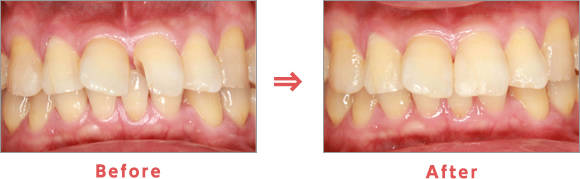

歯周病治療

さまざまな要因を改善することが歯周病治療の始まりです。

まずはカウンセリングやブラッシング指導で生活習慣やセルフケアの改善を行い、超音波やスケーラーなどさまざまな器具を使って歯周病の原因である歯石を取り除いていきます。

Before:歯と歯ぐきの境目に歯垢や歯石が付着し、歯ぐきが赤く腫れています。

Brushing:ブラッシング指導を行い、歯ぐきの腫れを改善します。

Treatment:歯石を取り除くことで、歯ぐきの慢性炎症を消炎します。

After:赤くなっていた歯ぐきは健康なピンク色に改善されています